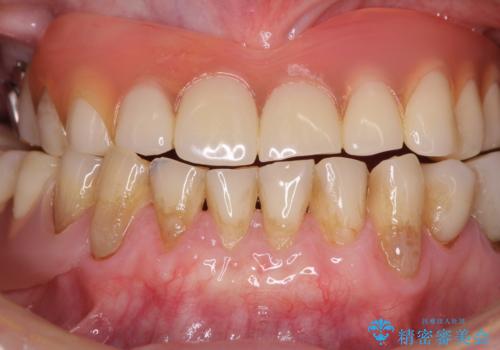

- 咬み合わせにより下の前歯の歯肉が退縮してしまい、根が見えていることが気になるとのことで来院された患者様です。

歯肉退縮に対して、上顎からの結合組織移植術(CTG)により、歯根の被覆を行うとともに、歯肉の厚みを増すことで将来の退縮リスクを抑制することとしました。

歯肉が大変薄かったため、歯肉移植による根面被覆の効果はそれほど高くないように思われましたが、想像以上に歯肉の位置を回復させることができました。

歯肉の厚みも十分に獲得でき、患者様には大変満足していただきました。